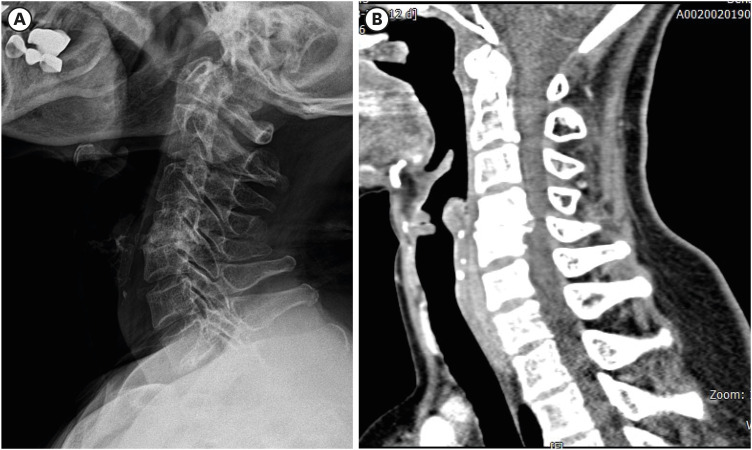

虽然颈椎椎间盘切除前路融合术(ACDF)是治疗颈椎病最常见的手术之一,但它也与各种术后并发症有关。食管穿孔是一种罕见但非常严重的 ACDF 术后并发症,而螺钉从口腔挤出的病例则更为罕见。在此,我们介绍了一名 61 岁女性的病例,她在接受 ACDF 手术 6 个月后因螺钉从口腔挤出而到我们的急诊中心就诊。虽然影像诊断没有证实食管穿孔,但螺钉经口挤出是并发症的明显证据。据我们所知,这是第一例未确诊食管损伤的口腔螺钉挤出病例。该病例表明,螺钉移位和食管穿孔的发生取决于患者的基础情况,如果症状轻微,仅靠保守治疗可能就足以治疗穿孔。

Although anterior cervical discectomy and fusion (ACDF) is one of the most common surgical procedures performed for the treatment of cervical disease, it is associated with a variety of postoperative complications. Esophageal perforation is a rare but very serious post-ACDF complication, and cases in which screws extrude through the mouth are even rarer. Herein, we present the case of a 61-year-old woman who visited our emergency center with oral extrusion of a screw 6 months after undergoing ACDF. Although diagnostic imaging did not confirm esophageal perforation, the oral extrusion of the screw was clear evidence of the complication. To the best of our knowledge, this is the first reported case of oral screw extrusion without confirmed esophageal injury. This case suggests that screw migration and esophageal perforation can occur depending on the patient's underlying condition, and if the symptoms are mild, conservative treatment alone may be sufficient to treat the perforation.